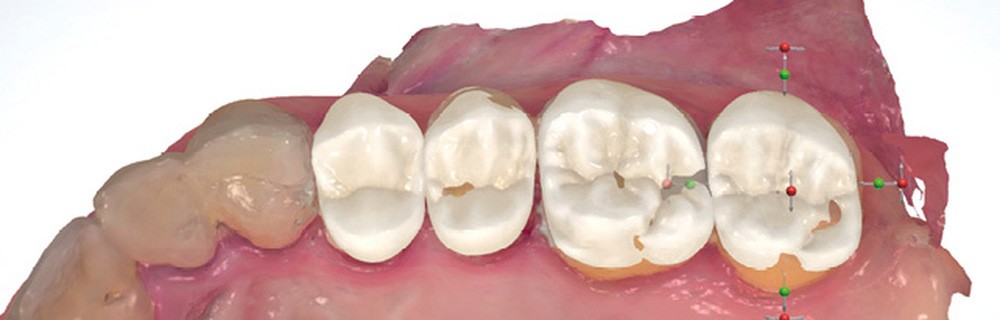

Enfin, des outils d’analyse sont de plus en plus présents avec les systèmes d’empreinte, notamment pour analyser les épaisseurs préparées (avec des outils de coupe) ou pour étudier le parallélisme entre des dents dans les cas de bridge (fig. 2).

La corrélation de fichiers est un vrai facilitateur pour les plans de traitement prothétique ; que ce soit pour le suivi des cas, ou dans des cas particuliers comme celui de la couronne sous châssis. Cette situation est toujours préjudiciable pour le patient en empreinte conventionnelle, car elle oblige à priver ce dernier de sa prothèse adjointe le temps que le laboratoire conçoive la couronne. Avec l’empreinte optique, il suffit d’enregistrer le crochet et sa position par rapport à la préparation pour que le prothésiste puisse concevoir une prothèse adaptée à la cavité buccale et à la prothèse amovible. Autre cas particulier, lors de la réalisation d’inlay-core, les logiciels de laboratoire ont des algorithmes qui autorisent la conception en seul temps de l’inlay-core et de la couronne avec un calcul des morphologies des éléments pour qu’ils respectent à la fois l’homothétie et les épaisseurs minimales de matériau (fig. 3 et 4).